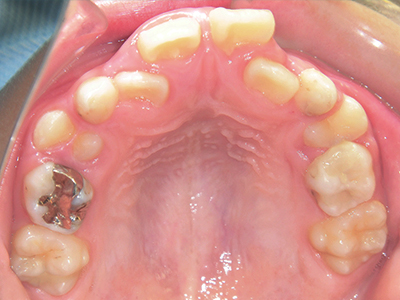

ないき歯科クリニックでは、上あごの成長不足を補い、鼻呼吸を獲得しつつ歯列を整え、将来のお口をより健康な状態にすることをゴールに定める矯正治療をおこなっています。